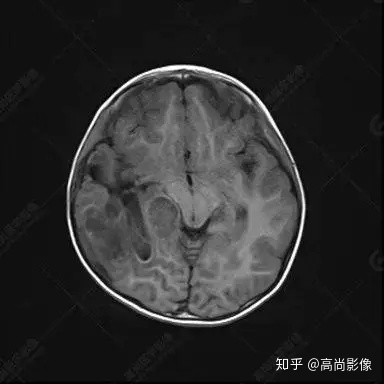

右側(cè)顳葉腫瘤切除術(shù)后(具體不詳):右側(cè)顳部骨質(zhì)不連續(xù)呈術(shù)后改變,右側(cè)顳葉術(shù)區(qū)見片狀長T1長T2信號影,F(xiàn)LAIR呈低信號;術(shù)區(qū)后方右側(cè)顳枕葉見一巨大占位性病變影,邊界欠清,大小約6.2×5.8×4.3cm(前后×左右×上下),信號不均勻,T1WI呈等稍低信號間雜少許高信號,T2WI呈高稍低混雜信號,DWI示部分病灶彌散受限,相應(yīng)ADC圖減低,磁敏感序列見部分呈極低信號,增強(qiáng)掃描可見明顯不均勻強(qiáng)化,鄰近硬腦膜及小腦幕增厚并明顯強(qiáng)化;另延髓右前方及右側(cè)橋小腦角區(qū)見一不規(guī)則形異常信號影,大小約3.2×1.3×3.7cm(左右×前后×上下),呈長T1稍長T2信號,F(xiàn)LAIR呈等信號,DWI未見受限,增強(qiáng)后明顯均勻強(qiáng)化,鄰近腦膜明顯強(qiáng)化。鄰近腦實質(zhì)及右側(cè)顳角明顯受壓;左側(cè)大腦半球未見局灶性信號異常,中線結(jié)構(gòu)稍左移。

右側(cè)顳葉腫瘤切除術(shù)后:現(xiàn)術(shù)區(qū)后方右側(cè)顳枕葉及延髓右前方占位,右側(cè)顳枕部硬腦膜及小腦幕明顯強(qiáng)化,結(jié)合既往影像資料,考慮為胚胎源性惡性腫瘤,如非典型畸胎樣/橫紋肌樣瘤(AT/RT)或原始神經(jīng)外胚層腫瘤(PNET)。

術(shù)后隨訪病理結(jié)果:非典型畸胎樣/橫紋肌樣瘤。